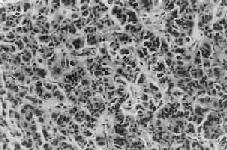

二、胰岛细胞瘤胰岛细胞瘤(islet-cell tumor)由于其构成细胞不同,所分泌的激素和引起的症状也不同。有一部分肿瘤乃无功能性肿瘤,临床上不出现任何特殊症状。胰岛细胞瘤在HE染色片上不可能区分出细胞的种类,常需借助特殊染色、电镜及免疫组化技术来加以鉴别。 1.B细胞肿瘤 从胰岛B细胞(即B细胞)发生的肿瘤有腺瘤和腺癌;其中一部分能分泌胰岛素,可称之为insulinoma,临床上可有低血糖症状。大约80%是单发性腺瘤,10%为多发性腺瘤,10%是癌。本瘤可见于各个年龄层,但以40~50岁为多见。肉眼观,一般以胰体及胰尾部为多见,有完整包膜,大小为0.5~10cm,切面色微黄。组织学上,瘤细胞似胰岛细胞,呈多角形或柱状,胞浆颗粒状,细胞排列成条索或巢状,有时可出现菊形团排列。周围绕以血窦(图15-19)。间质中常出现淀粉样物质或钙盐沉积。其恶性者称为胰岛细胞癌。但由于肿瘤细胞常可因变性而出现多形性和奇异形核,因而从镜下区分良恶性有时也颇困难,常需根据其浸润性生长和淋巴结、肝转移等才能做出判断。

图15-19 胰岛细胞瘤 2.Zollinger–Ellison综合征本综合征以胰岛细胞瘤、大量胃酸分泌和溃疡病为主征。肿瘤常为多发性,60%是恶性,细胞大小不一,瘤细胞分泌胃泌素,故又称胃泌素瘤(gastrinoma)。在胰岛该瘤细胞来源不明。此瘤可见于胰腺任何部位,也可发生在十二指肠及胃幽门窦部。由于胃泌素的作用,胃酸分泌亢进,导致溃疡病形成。溃疡主要见于十二指肠及胃,但25%可出现在空肠。患者还常有水样腹泻及脂性腹泻。